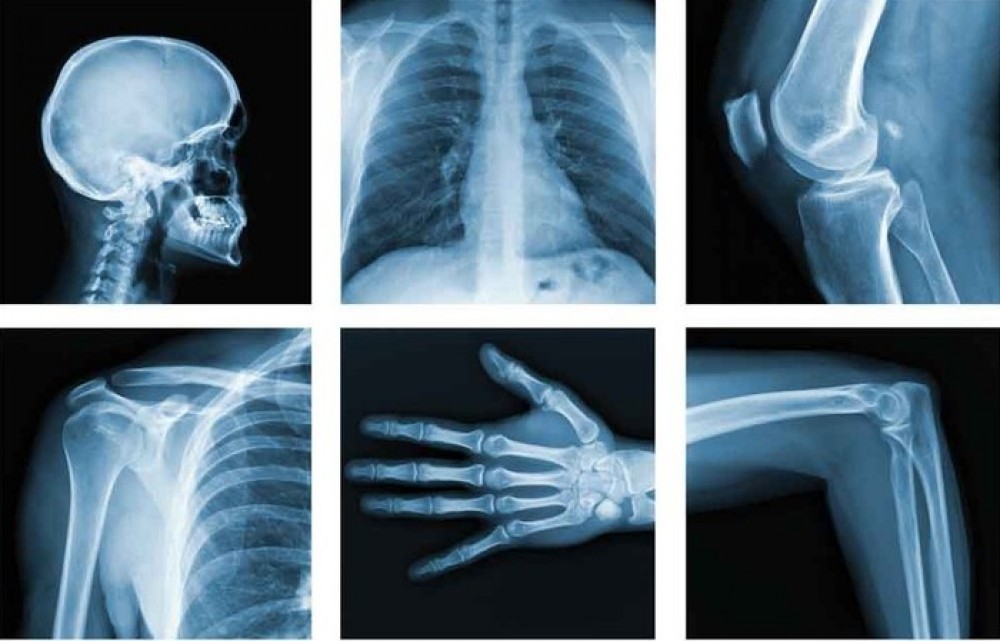

Способность рентгеновских лучей просвечивать материальные объекты не только дает людям возможность создавать простые рентгеновские снимки, но и открывает возможности для более продвинутых средств диагностики. К примеру, она лежит в основе метода компьютерной томографии (КТ).

Внутри кольца, в котором лежит пациент, вращаются источник рентгеновских лучей и приемник. Полученные данные о том, как ткани тела поглощают рентгеновские лучи, реконструируются компьютером в 3D-картинку. Метод КТ особенно важен для диагностики инсульта, и хоть он и менее точен, чем магнитно-резонансная томография головного мозга, зато требует гораздо меньше времени.

Сравнительно новое направление, которое развивается сейчас в микробиологии и медицине, — применение мягкого рентгеновского излучения. При просвечивании живого организма оно позволяет получать изображение кровеносных сосудов, подробно изучать структуру мягких тканей и даже проводить микробиологические исследования на клеточном уровне.